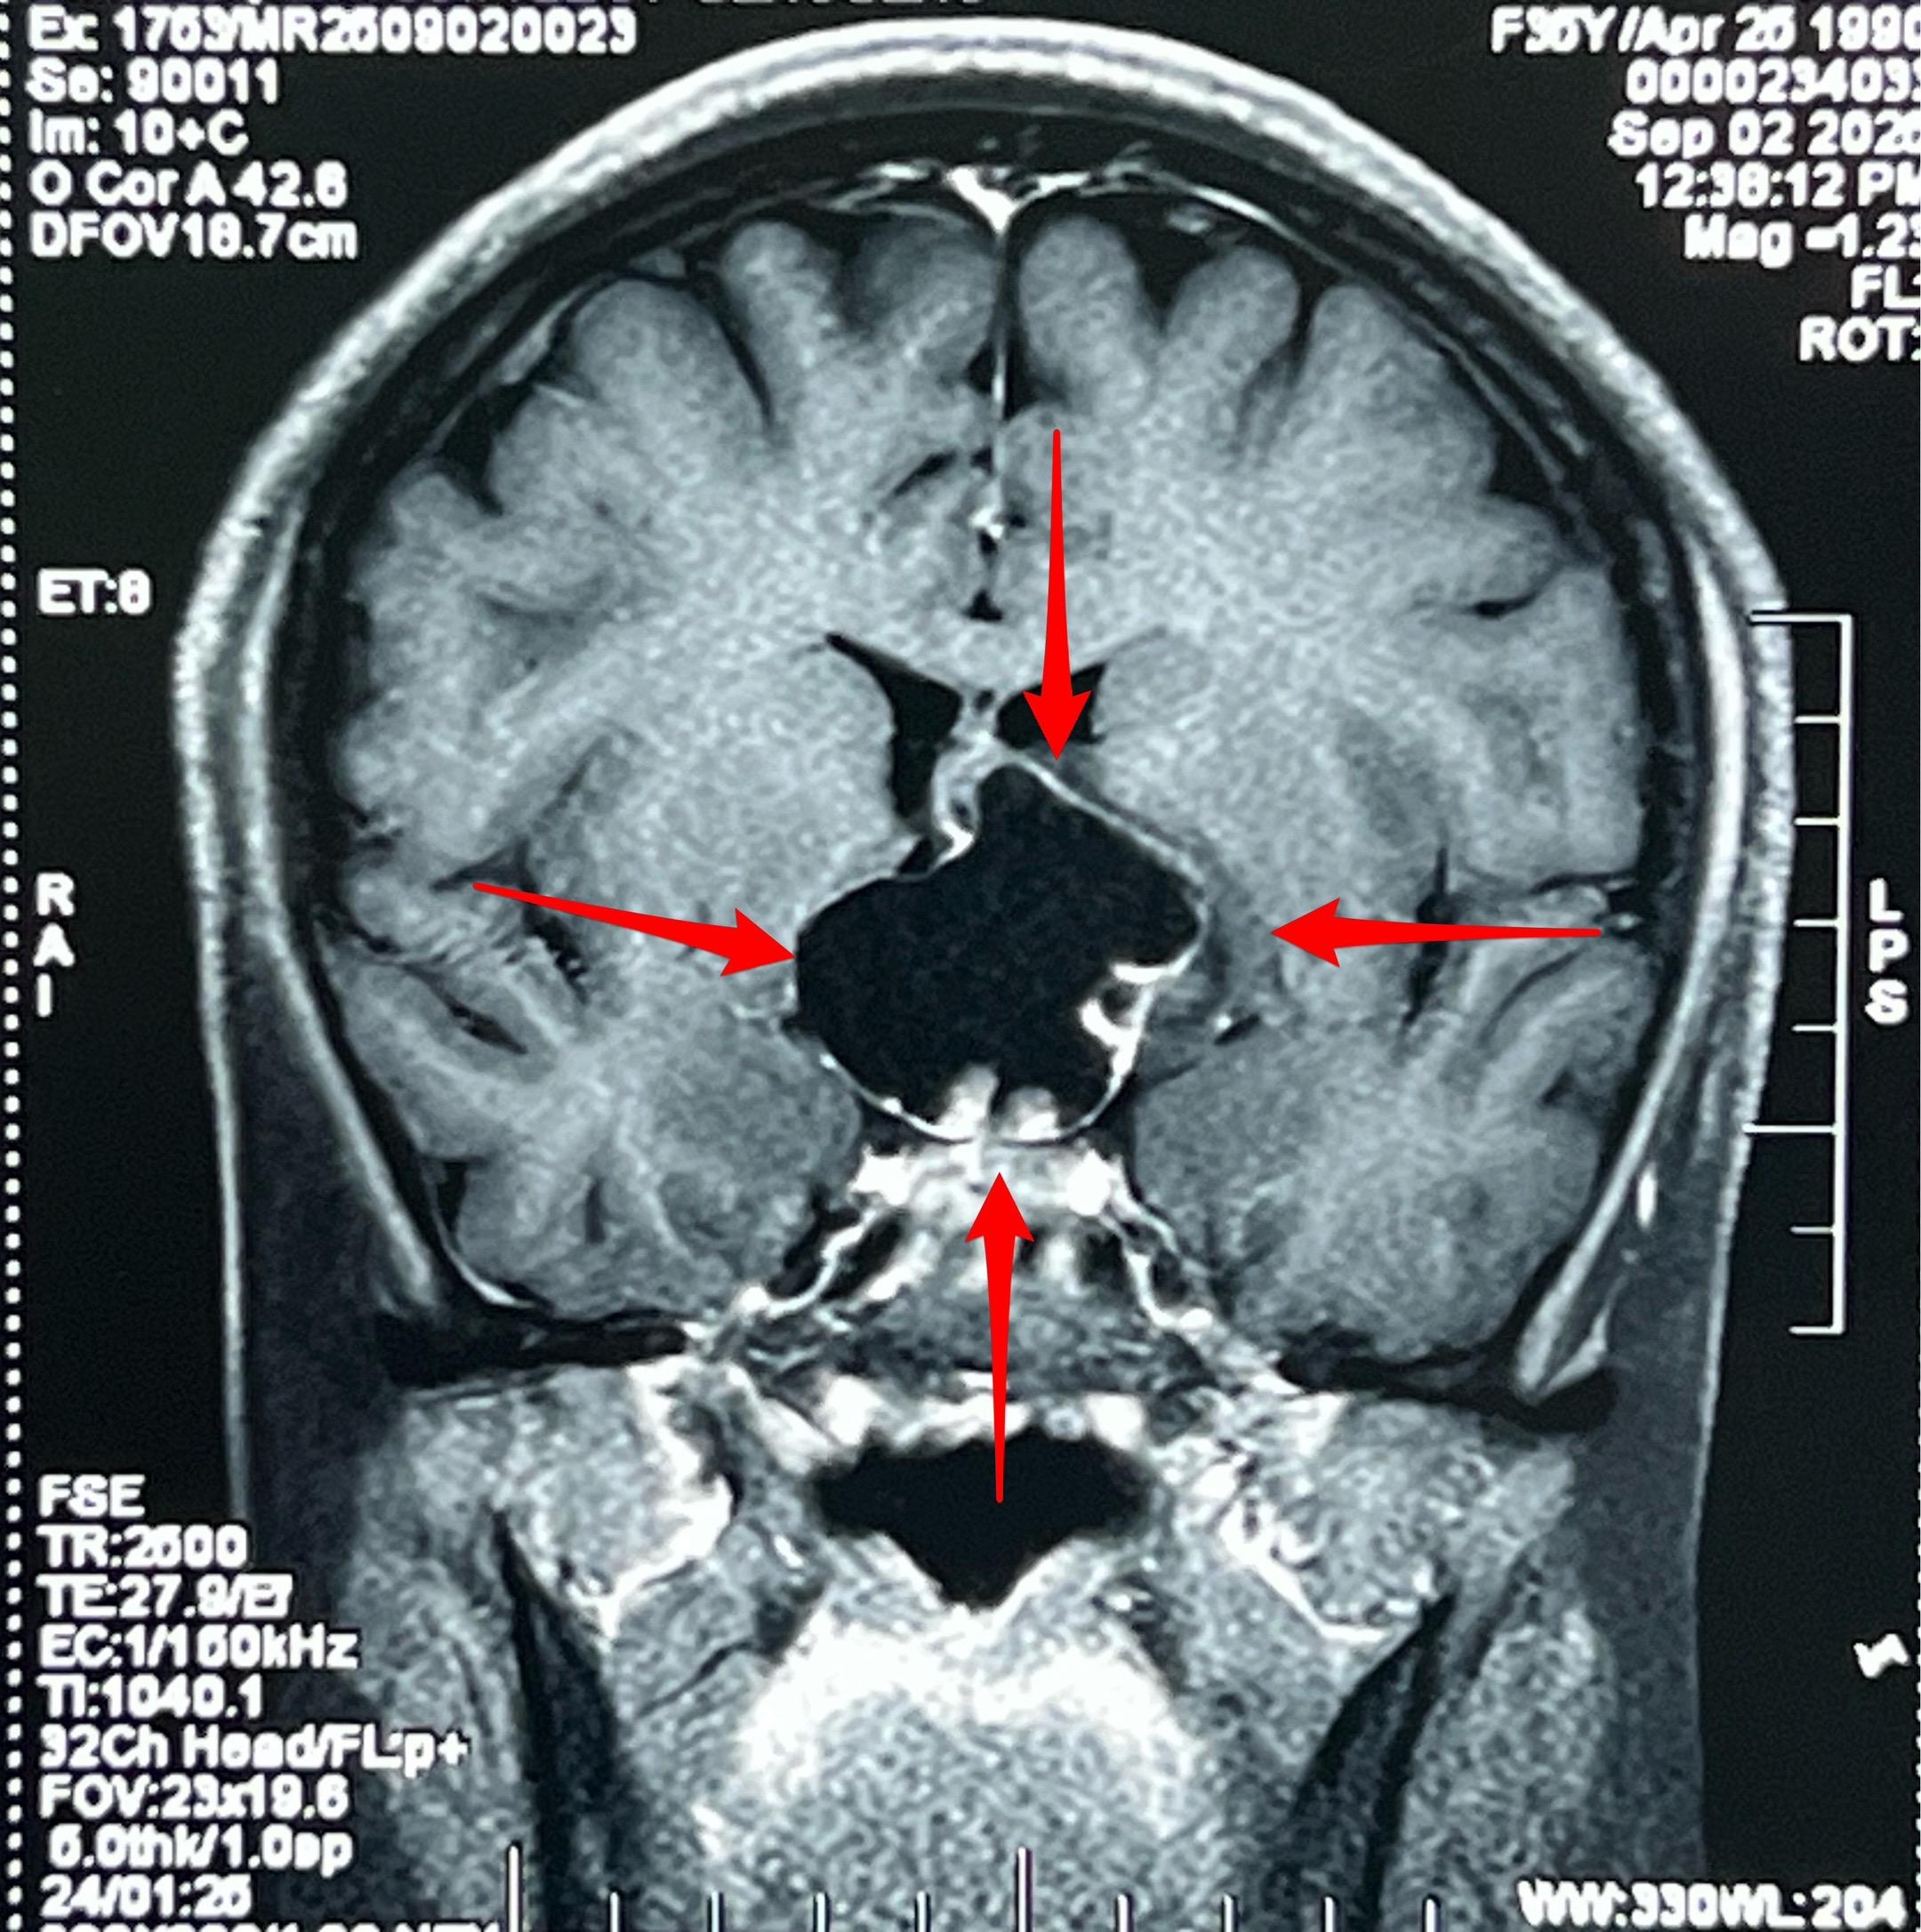

颅咽管瘤的症状科普。之前我多次讲过颅咽管瘤的症状,结合这个病人再说一次。 这个35岁女性在2025年8月发现了颅咽管瘤。 她两年前最开始出现生理周期紊乱、停经,这是下丘脑-垂体受损伤导致的内分泌系统功能障碍的表现。 一年前患者出现视力下降,越来越严重,一直到没有有效视力了才去就医,才发现这个颅咽管瘤。这是视神经-视交叉受到肿瘤压迫造成的。 在视力下降的同时病人出现长胖,体重显著增加。这也是下丘脑受损的表现。 病人在就诊